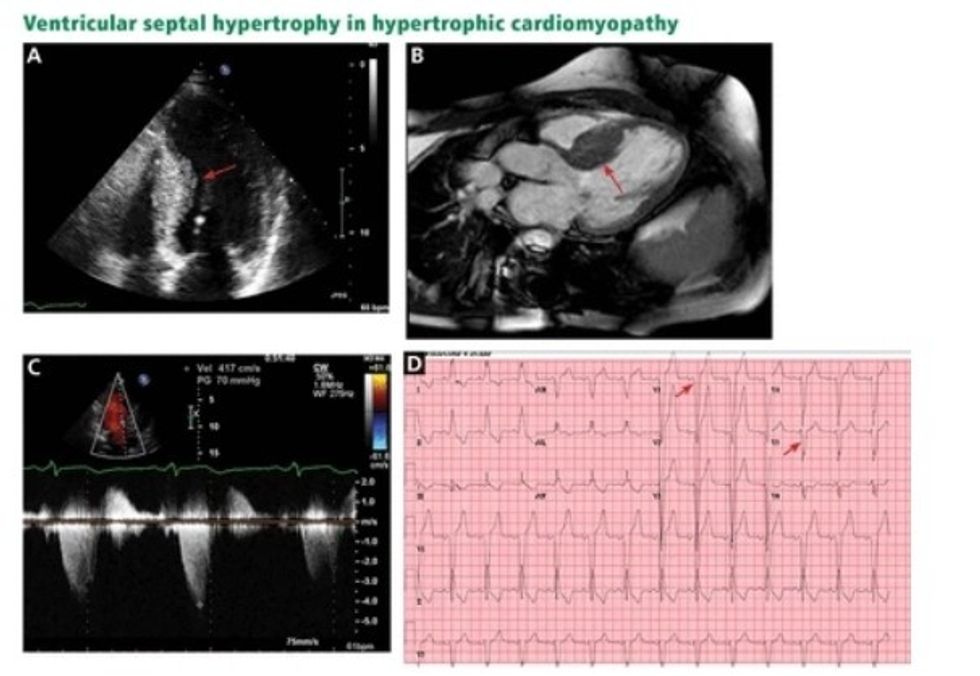

Kardiomiopatia hipertrofike është një gjendje në të cilën vërehet trashje e shtuar (hipertrofi) e barkushes së majtë me përmasa të septumit interventrikular mbi 15 mm, pa një arsye specifike dhe të qartë. Me fjalë të tjera, hipertrofia nuk është për shkak të hipertensionit arterial ose stenozës së aortës. Është karakteristike se hipertrofia është asimetrike, barkushja e majtë ka një zgavër të vogël, ka një gradë presioni të rritur midis barkushes së majtë dhe daljes së saj, dhe indi i muskujve kardiak ka një pamje të njollosur. Sëmundja shfaqet si rezultat i mutacioneve në gjenet që kodojnë proteinat sarkomerike kardiake.

Për diagnostikimin e kësaj gjendjeje kryesisht përdoret elektrokardiografia (EKG) dhe ekokardiografia, e cila në fakt është metoda kryesore (më e zakonshme) diagnostike përmes së cilës vërtetohet sëmundja. Gjithashtu, merret parasysh aplikimi i monitorimit 24-48 orësh të ritmit të zemrës Holter, ekokardiografisë së stresit dhe rezonancës magnetike të zemrës.